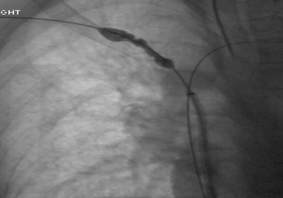

Snaring of Wire